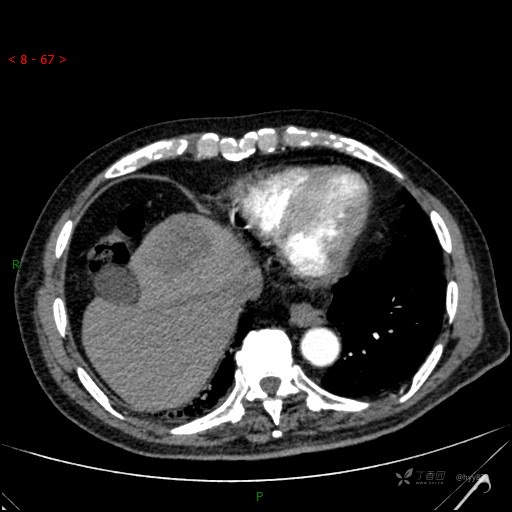

延迟期

img

肝脓肿 (73)